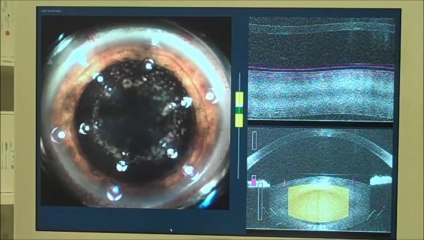

For the Eye Institute of West Florida Visit:   | Contact us at 800-494-3937. The Eye Institute of West Florida was founded by Stephen Weinstock, MD in 1974. For more than thirty five years, our practice has provided excellence in eye care in a warm, personal environment combined with a tradition of service and devotion to our patients. br br Cataract Laser Surgery is the most commonly practiced procedure to correct vision problems caused by refractive errors including myopia, hyperopia and astigmatism. It is a procedure that most eye doctors are familiar with. It reduces risks of anything going wrong as the procedure itself is quick and painless. The Eye Institute of West Florida offers numerous benefits and can dramatically improve the quality of life of a person as most people achieve 2020 vision or better after the surgery. To know more about Eye Institute of West Florida visit: br br Cataract surgery is the only way to correct cataracts. The procedure involves the removal of the clouded lens and replacing it with an artificial intraocular lens. It is a simple and safe procedure with a very high success rate. The procedure itself usually lasts only 5 to 8 minutes. How well you see after surgery will vary. Outcomes can depend on lens selection, OR technology, and the surgeon’s experience. br br Here at the Eye Institute of West Florida we specialize in providing cataract patients custom lens options that are designed to help them see clearly at all ranges of distance without the aid of glasses and contacts all the time. Because every eye is uniquely different, we offer a multitude of specialty lenses that meet the custom need of each individual patient. Our operating rooms are equipped with the world’s finest vision systems. It is quite possible we are the only facility with not one, but two femtosecond cataract laser units and among very few ambulatory surgery centers in the United States with a real-time refraction system. br br With 3 convenient locations; Our Doctors and experienced staff are here to answer any questions that you may have. To know more about the Eye Institute of West Florida visit: or call 800-494-3937. Our offices are located in Largo FL, Clearwater FL, and St. Petersburg FL and we serve patients throughout the State of Florida. br br Location Addresses: br br 148 13th Street SW Largo FL 33770 – Telephone # - 727-581-8706 br 6133 Central Avenue, St.